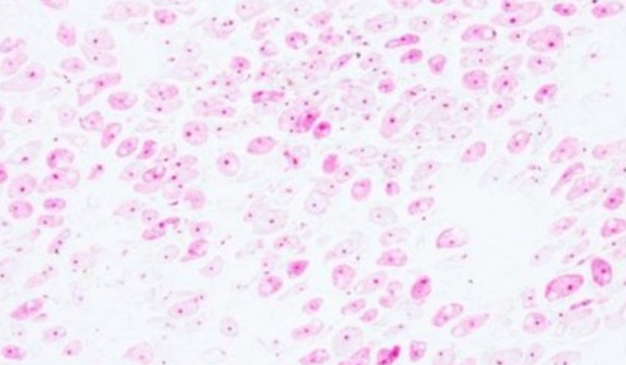

Entamoeba histolytica - trofozoit

40x